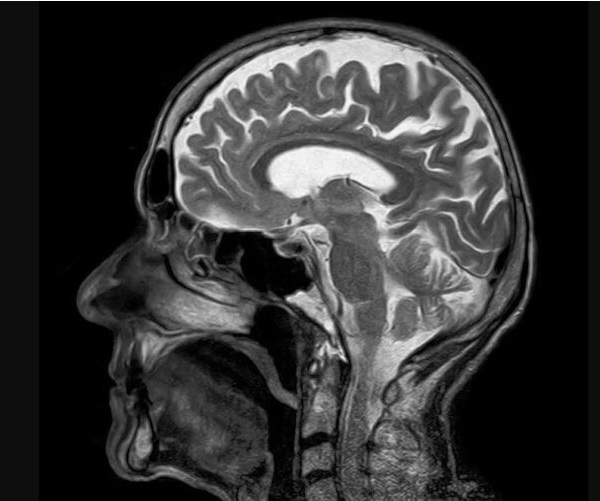

Razmere, ki prizadenejo živčni sistem – kot so možganske kapi, migrene in demenca – so prehitele bolezni srca in postale glavni vzrok za slabo zdravje po vsem svetu, je v petek pokazala velika nova analiza.

Več kot 3,4 milijarde ljudi – 43 odstotkov svetovnega prebivalstva – bo leta 2021 doživelo nevrološko bolezen, kar je veliko več, kot se je domno doslej, je pokazala analiza.

Vodilni avtor študije Jaimie Steinmetz iz IHME je dejal, da rezultati kažejo, da so bolezni živčnega sistema zdaj "glavni svetovni vzrok za celotno breme bolezni".

Raziskovalci so preuči, kako 37 različnih nevroloških stanj vpliva na slabo zdravje, invalidnost in prezgodnjo smrt v 204 državah in ozemljih od leta 1990 do 2021.

Možganska kap, ki je prej veljala za bolezen srca, je bila daleč najhujše analizirano nevrološko stanje, kar je povzročilo izgubo 160 milijonov let zdravega življenja.

Spremljala ga je oblika poškodbe možganov, imenovana neonatalna encefalopatija, migrene, demenca, vključno z Alzheimerjevo boleznijo, poškodbe živcev zaradi sladkorne bolezni, meningitis in epilepsija.

Glede na študijo v The Lancet Neurology je leta 2021 zaradi 37 nevroloških bolezni umrlo več kot 11 milijonov ljudi.